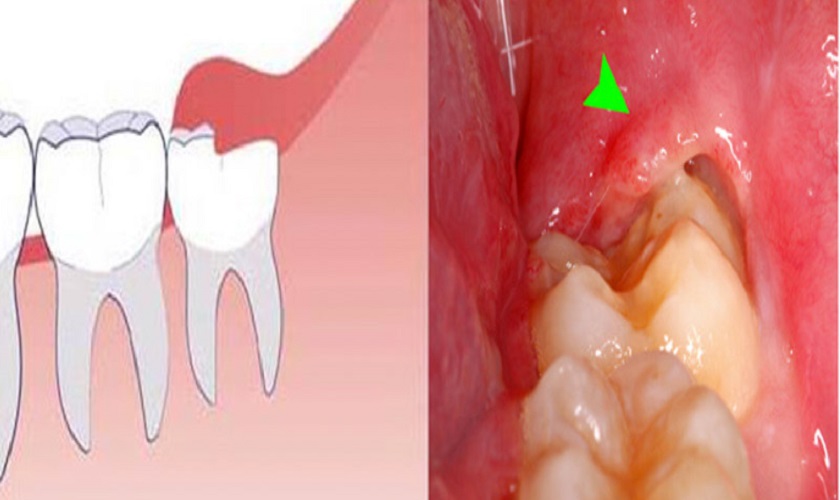

Mọc răng khôn có thể gây đau nhức do nhiều nguyên nhân khác nhau. Một trong những nguyên nhân phổ biến là không gian hạn chế trong hàm, khiến răng khôn không có đủ không gian để phát triển hoàn toàn. Do đó, răng khôn có thể mọc nghiêng, chen ép vào các răng lân cận hoặc bị kẹp giữa xương hàm và lớp niêm mạc, gây ra cảm giác đau nhức và sưng đau. Ngoài ra, việc nhiễm trùng xung quanh vùng răng khôn cũng có thể gây ra đau nhức và viêm nhiễm, khiến cho quá trình mọc răng trở nên đau đớn và khó chịu.

Răng khôn mọc lệch có thể làm cho việc làm sạch vùng nướu trở nên khó khăn, dễ dẫn đến viêm nướu trùm và viêm nhiễm tại chỗ. Việc này có thể gây ra đau đớn, sưng phù và kích thích nướu.

Gây sâu răng số 7 bên cạnh

Nếu răng khôn mọc lệch hướng vào răng số 7 bên cạnh, nó có thể tạo ra một khe hở giữa các răng, dễ dẫn đến việc mảng bám và thức ăn tích tụ, tăng nguy cơ phát triển sâu răng và viêm nhiễm.